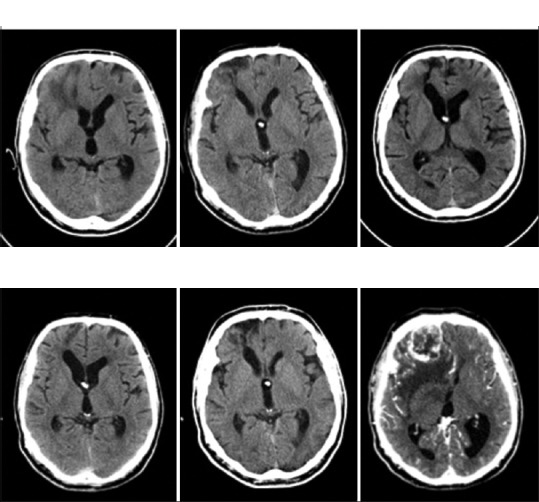

兒童腦瘤是怎么引起的原因?腦部創(chuàng)傷與腦瘤有關(guān)系嗎?54歲的Lee,在一次車禍中右額葉下端嚴(yán)重挫傷(圖1)。受傷后不久,他患上了創(chuàng)傷后腦積水,并接受了右額腦室-腹腔分流術(shù)的治療。隨后,他需要放置心臟起搏器,這就妨礙了MRI成像。隨后對(duì)他進(jìn)行連續(xù)的計(jì)算機(jī)斷層掃描(CT),顯示挫傷的清晰度和右下額部腦軟化的發(fā)展。

受傷七年后,他因頭痛和神志不清再次接受治療。CT顯示在腦損傷部位有一個(gè)4厘米的異位增強(qiáng)的右下額部腫塊。病變周圍有廣泛的血管源性水腫。他接受了右額葉開顱手術(shù),以完全切除腫塊,診斷為GBM。IDH1 R132H突變的免疫組化結(jié)果為陰性。隨后根據(jù)Stupp協(xié)議對(duì)其進(jìn)行了放化療。術(shù)后8個(gè)月的較新隨訪顯示,其神經(jīng)系統(tǒng)完好,CT沒(méi)有復(fù)發(fā)跡象。

圖1:連續(xù)73個(gè)月的電腦斷層掃描顯示右下額葉的膠質(zhì)母細(xì)胞瘤在挫傷部位發(fā)生。